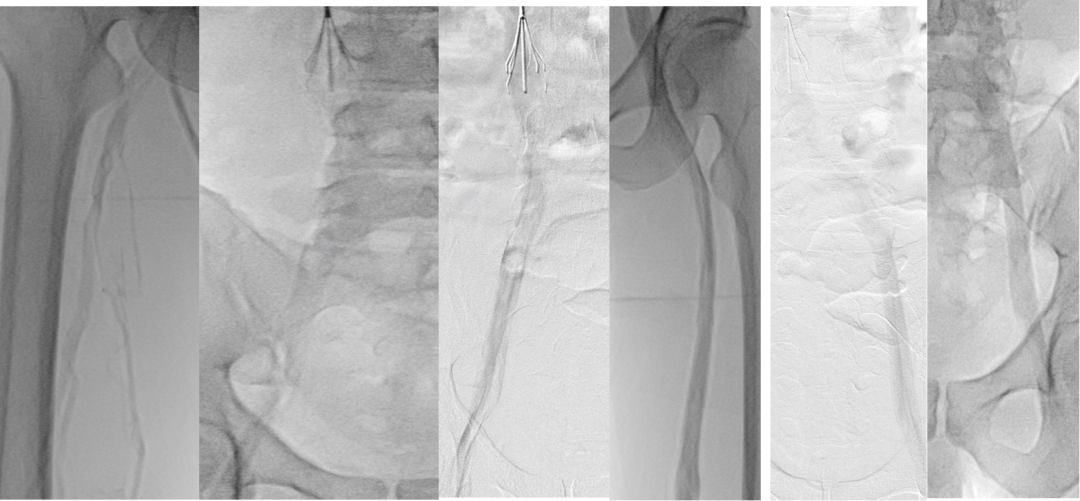

★ Case2:滤器相关慢性血栓闭塞开通后KISS支架

髂静脉支架置入术后研究:PTS中远期通畅率并不高

对于部分年轻患者,采取首期多次重复球囊扩张的策略。基于“闭塞通常发生在术后1-1.5个月”的观察,他们在第一次治疗后的1个月、1个半月左右进行二次、三次扩张。初步数据显示,这种策略能使一年期的血管通畅率超过70%,为患者保留了宝贵的自体血管通路,避免了过早植入支架。

★ Case4:慢性IVCT腔髂静脉治疗

图:第一次:扩张下腔静脉、髂静脉并取出滤器2025.2.13

图:二次复查CT并进行球囊扩张2025.3.31

图:早期复查结果比较满意(一年期通畅率>70%)